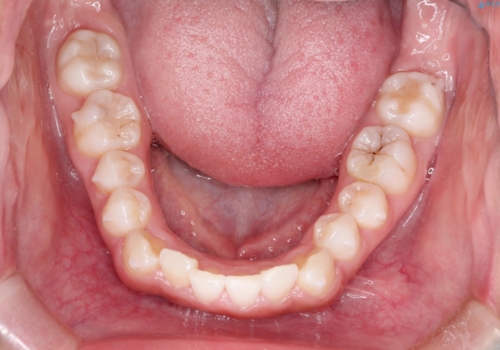

- 初診時には前歯部に捻転や叢生、臼歯部にも一部叢生が見られる状態でした。

インビザラインでの治療を計画し、行っていきました。

インビザライン治療により、捻転を含む歯列もしっかりと改善しています。

基本的な不正咬合部分は初回の30枚のマウスピースでほぼ改善しており、リファインメントでは前歯部の細かな調整など、患者様の要望を取り入れる形でシミュレーションをセットアップし、満足の行く結果に仕上がりました。